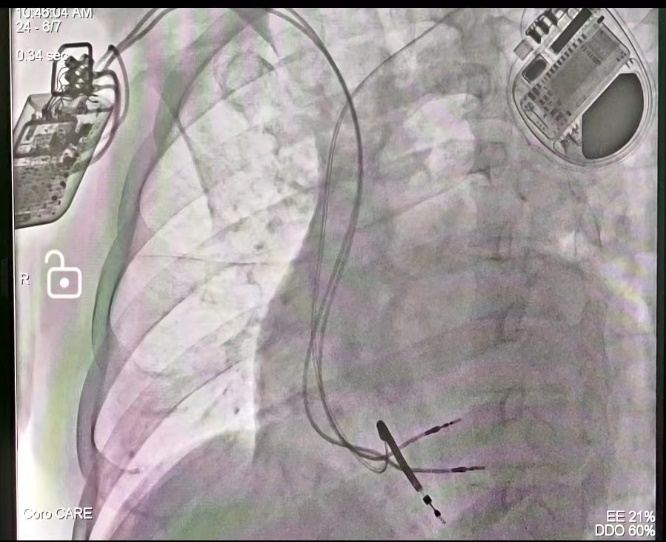

手术在局麻下进行,ICD植入在左侧,CCM植入在右侧。需要在患者右心室内同时植入三根电极,并且要求在CCM两根电极间距大于2cm的同时,CCM和ICD电极彼此间距不小于3cm,如此才能最大程度地确保ICD和CCM正常工作,可以保证除颤的效果同时避免信号相互干扰,手术过程顺利。

三根导线的精准放置对此次手术尤为关键,也是技术的难点。高江峰主任等凭借着丰富的操作经验和精湛的导线操控技术,在团队人员的密切配合下,从左侧完成近心尖部除颤电极的植入后,从右侧先后植入两根主动起搏电极于右室间隔。植入后的三根电极位置非常理想,术中测试两根起搏电极的起搏阈值分别是1.0v(RV)和0.8v(LS),感知阈值分别是16.0mv(RV)和20mv(LS),起搏阻抗均低于1200Ω,提示电极准确植入在健康心肌上。联合测试三根电极均可以正常工作且彼此无干扰。